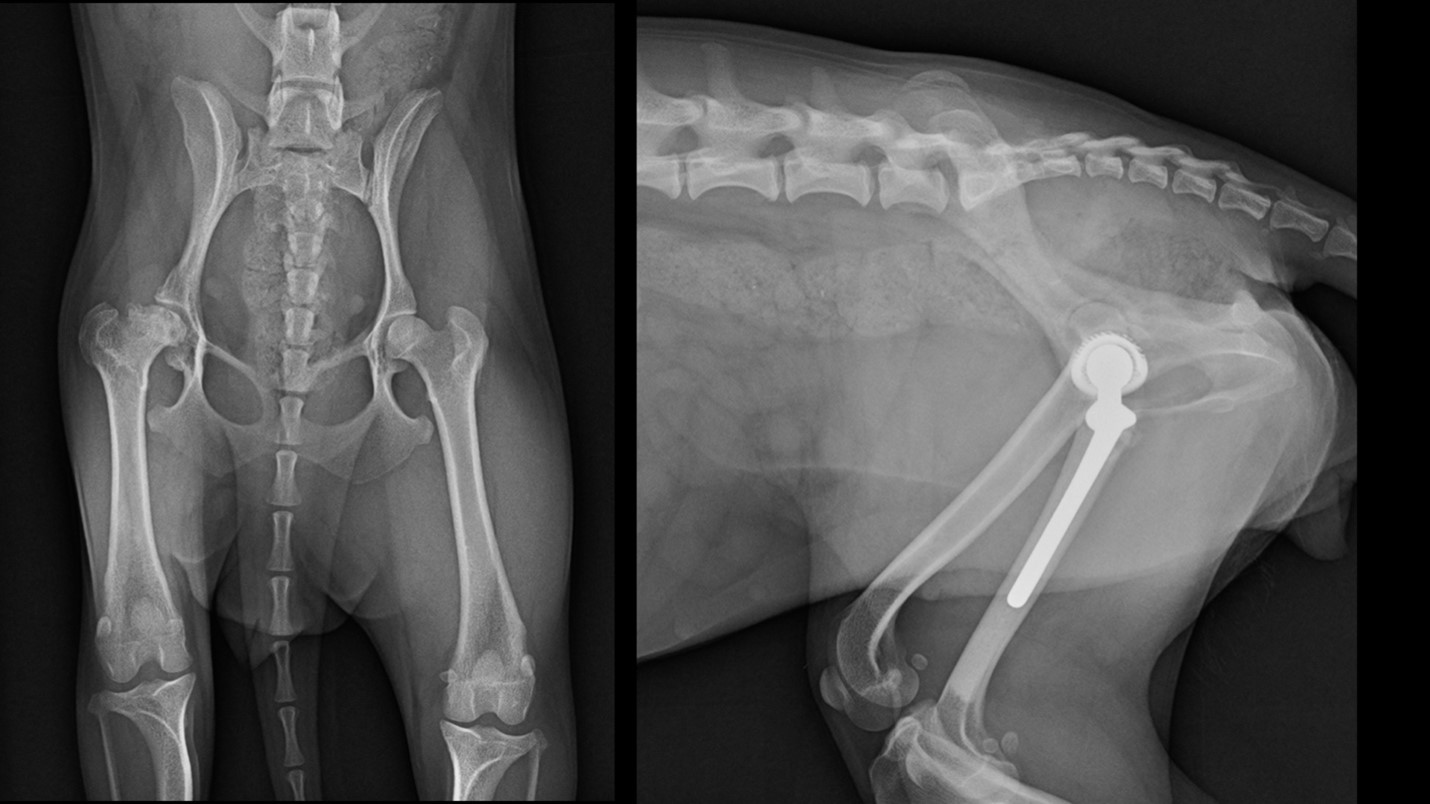

In many ways, the treatment of orthopedic conditions in toy dog breeds is still very much an evolving facet of veterinary science. Treatment modalities for toy dog breeds are increasingly paralleling those for standard and large breed dogs. Hip replacements are a prime example. There is an old—and unproven—adage among some veterinarians that small breed dogs do not have the mechanical need for hip replacements and that these breeds will function just fine with a false hip joint resulting from a femoral head ostectomy (FHO).

Traditionally, an FHO would have been the go-to therapy for conditions like avascular necrosis of the femoral head. However, it has never been well-documented that the outcomes are consistently positive, and there is mounting evidence that an FHO, while still commonly performed for small toy dog breeds, is probably not the best standard of care to offer to these animals. At the same time, more and more evidence shows that hip replacements in tiny dogs are regularly successful. In fact, there are now several joint replacement systems available for veterinary use that can be applied to toy breed dogs.